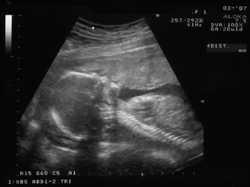

- Ekografija je tehnika registriranja ploda u maternici primjenom ultrazvuka. Mogu se uočiti anatomija i funkcionalnost ploda te eventualne nepravilnosti. Metoda je bezopasna po majku i dijete.